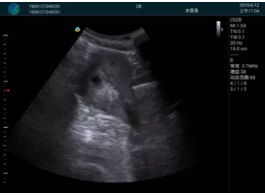

清晰顯示孕囊,通過(guò)軟件包計(jì)算孕齡7w+6d

M20實(shí)時(shí)引導(dǎo),術(shù)中清晰顯示孕囊被破壞和抽吸針的過(guò)程,清晰顯示吸引針

抽吸結(jié)束后縱切子宮,孕囊已被完全抽吸,未見(jiàn)明顯殘留

橫切子宮,發(fā)現(xiàn)右側(cè)宮腔靠近宮角處有少許脫模樣殘留